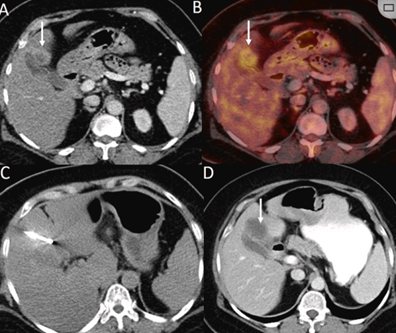

79 岁男性,肝转移(结直肠癌)肿瘤的完全消融病例

( a ) 轴向 MRI 和 ( b ) 轴向 CT 显示肝S8段有一个16mm的病灶,邻近肝缘。( c )冷冻消融期间CT显示放置了2个冷冻探针,低密度冰球包围病灶。(d)术后1个月随访 CT显示冰球对应的坏死区域,未见复发。(f)与基线影像(g)相比,12个月后的FDG-PET/CT显示未见FDG摄取。

(a)轴向CT显示病变位置毗邻心脏和上腔静脉(黑色箭头)。1个月后的轴向(e)和冠状位(f)增强CT扫描显示低密度区域,由于肉芽组织反应引起的边缘增强。